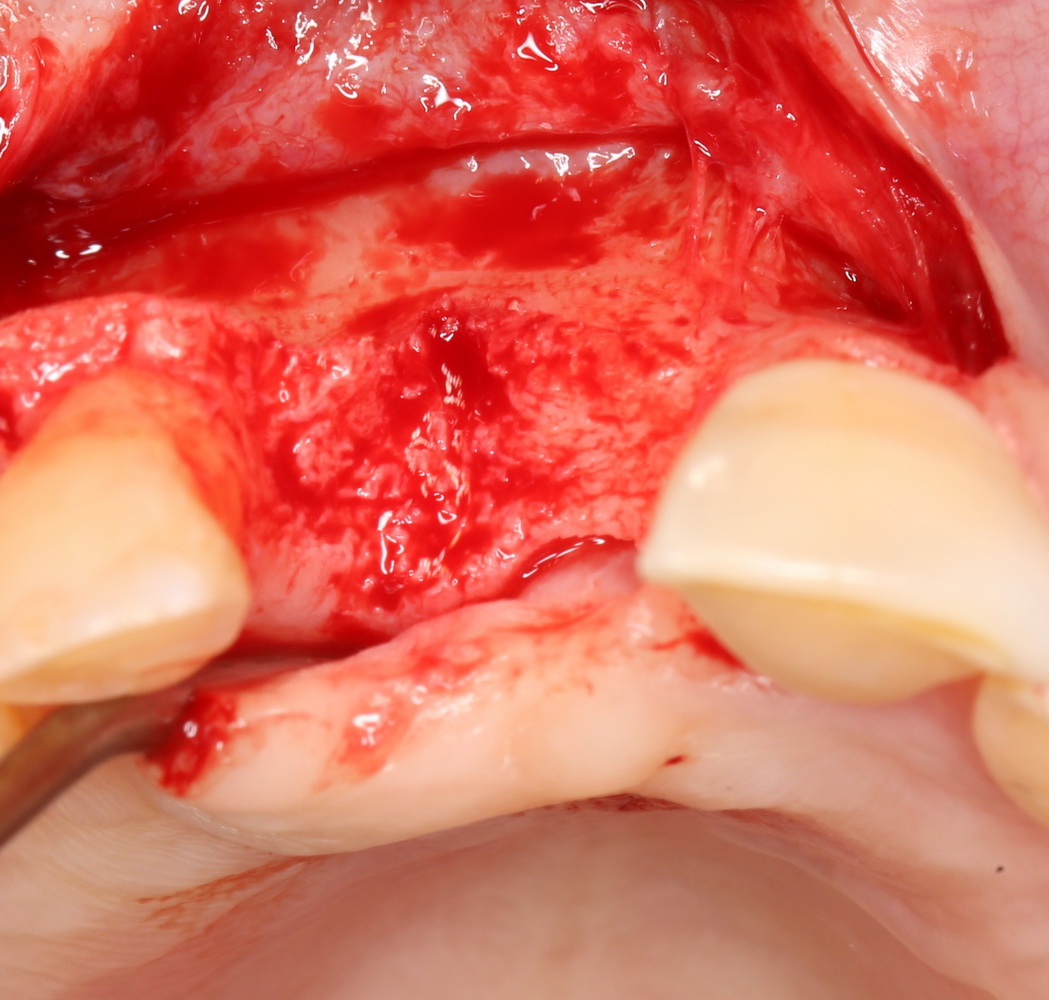

В этом случае остеопластика делается отдельной процедурой. Ее принципы точно те же, но уже без импланта. Например:

Имплантировать в таких условиях — заведомо обрекать себя на хреновый, с точки зрения эстетики и функциональности, результат. Поэтому первым этапом проводим остеопластику. Объем небольшой, использовать в таких объемах костный блок не очень рационально. Воспользуемся аутокостной стружкой и мембраной.

Сначала фиксируется BioGide. Это легко:

Затем укладывается и конфигурируется аутокостная стружка:

Если после этого BioGide намочить физраствором, им легко укрыть получившийся объем: